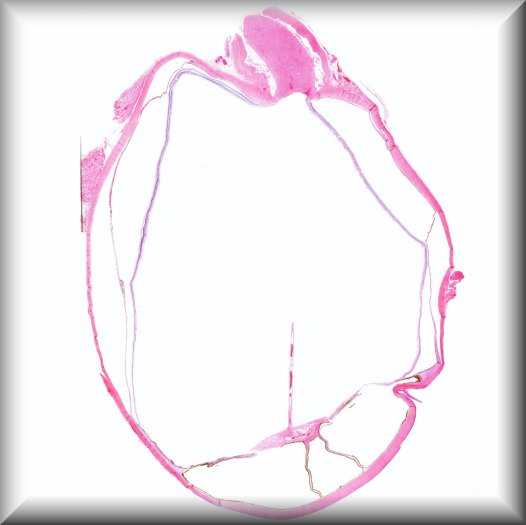

Claudia Auw-Haedrich: Vitreal opacities in a 56-year-old female with inherited Transthyretin amyloidosis. At the age of 41, our patient underwent a liver transplant due to hereditary transthyretin amyloidosis. Fifteen years later, she experienced visual deterioration to 0.5 in her left eye due to vitreous opacities. Protocol |